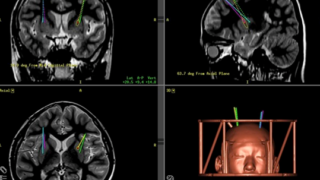

脂肪摂取は若年健康成人における精神的ストレス時の皮質酸素化を抑制する Fat Consumption Attenuates Cortical Oxygenation during Mental Stress in Young Healthy Adults

Mental stress has been associated with cardiovascular events and stroke, and has also been linked with poorer brain function, likely due to its impact on cerebral vasculature. During periods of stress, individuals often increase their consumption of unhealthy foods, especially high-fat foods. Both high-fat intake and mental stress are known to impair endothelial function, yet few studies have investigated the effects of fat consumption on cerebrovascular outcomes during periods of mental stress. Therefore, this study examined whether a high-fat breakfast prior to a mental stress task would alter cortical oxygenation and carotid blood flow in young healthy adults. In a randomised, counterbalanced, cross-over, postprandial intervention study, 21 healthy males and females ingested a high-fat (56.5 g fat) or a low-fat (11.4 g fat) breakfast 1.5 h before an 8-min mental stress task. Common carotid artery (CCA) diameter and blood flow were assessed at pre-meal baseline, 1 h 15 min post-meal at rest, and 10, 30, and 90 min following stress. Pre-frontal cortex (PFC) tissue oxygenation (near-infrared spectroscopy, NIRS) and cardiovascular activity were assessed post-meal at rest and during stress. Mental stress increased heart rate, systolic and diastolic blood pressure, and PFC tissue oxygenation. Importantly, the high-fat breakfast reduced the stress-induced increase in PFC tissue oxygenation, despite no differences in cardiovascular responses between high- and low-fat meals. Fat and stress had no effect on resting CCA blood flow, whilst CCA diameter increased following consumption of both meals. This is the first study to show that fat consumption may impair PFC perfusion during episodes of stress in young healthy adults. Given the prevalence of consuming high-fat foods during stressful periods, these findings have important implications for future research to explore the relationship between food choices and cerebral haemodynamics during mental stress.